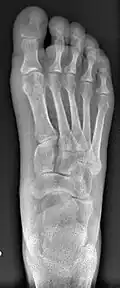

![]() Fig. 8a. Painful hallux valgus and metatarsus primus varus deformity recurrence of left foot after osteotomy surgery | |

- For recurrence correction after osteotomy procedure (Fig. 8)

Late deformity recurrence can happen after osteotomy (bone-breaking) procedures because osteotomy surgeries do not specifically stabilize first metatarsal bone.